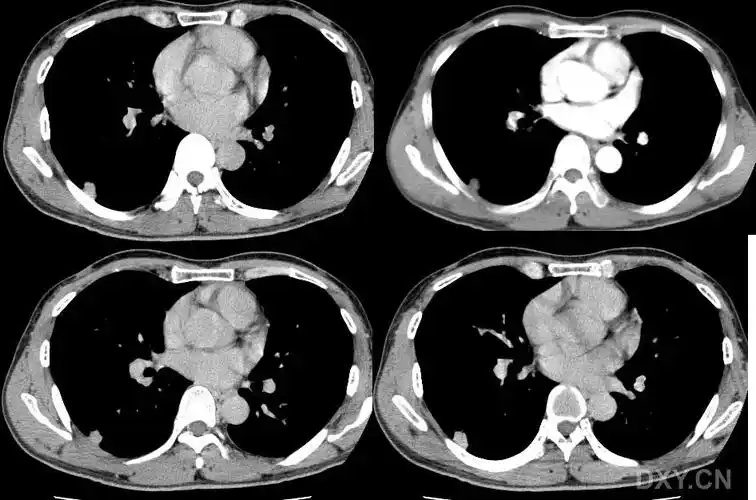

胸部ct平扫示左下肺占位肺癌